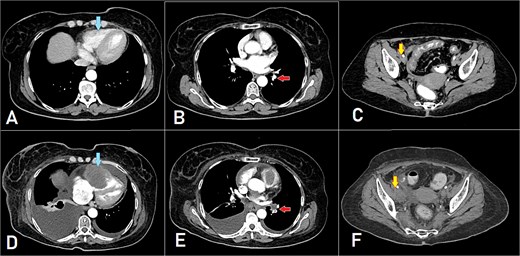

A computed tomography (CT) scan was performed, and the patient underwent a right hemicolectomy using a laparoscopic-assisted approach, with en bloc resection of the tumor and lymphadenectomy. The procedure was uneventful, with no intraoperative complications, and the patient had an unremarkable immediate postoperative recovery. The staging was determined as T4bN2bMx. Further imaging revealed enlarged mediastinal, supraclavicular, and retroperitoneal lymph nodes, with a solitary liver lesion (Fig. 1). A biopsy from the supraclavicular node indicated moderately differentiated adenocarcinoma of gastrointestinal origin. Molecular profiling showed wild-type RAS, intact MSI, mutant BRAF, and HER2 negative. The patient was started on capecitabine-oxaliplatin (CapeOX) with bevacizumab and completed 11 cycles with a marked clinical and radiological response (Fig. 2).

PET-CT scan (A) showing matted intensely hyper-metabolic left supraclavicular lymph nodes (arrow); (B) demonstrating intensely hyper-metabolic retroperitoneal lymph nodes (inferiorly pointing arrow) and a hyper-metabolic solitary hepatic lesion (superiorly pointing arrow); (C) demonstrating an intensely hyper metabolic mediastinal (para- oesophageal – station VIII) lymph node (arrow); and (D) revealing a few intensely hyper-metabolic retroperitoneal lymph nodes (arrow).